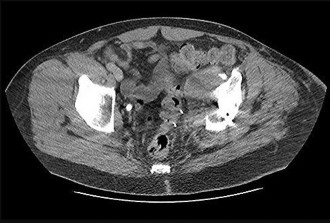

Figures 12a and 12b are a recent radiograph and a whole-body bone scan of an 81-year-old man who has hip pain and difficulty walking. His medical history is significant for obesity, hypertension, chronic kidney disease, and coronary artery disease. An examination demonstrates

moderate tenderness with passive range of motion of the left hip and an inability to actively flex the left hip against gravity. What is the best next step?

This patient has no known history of active malignancy. The radiograph shows a lesser trochanteric avulsion fracture (a fracture routinely associated with an underlying neoplasm). The bone scan reveals no other bone lesions. The femur fracture is statistically most likely to occur because of metastatic disease, but, without other evidence of metastasis, a primary bone sarcoma is possible, and biopsy is recommended before surgical fixation. Observation of this fracture, which is pathognomonic for neoplastic disease, is strongly discouraged.